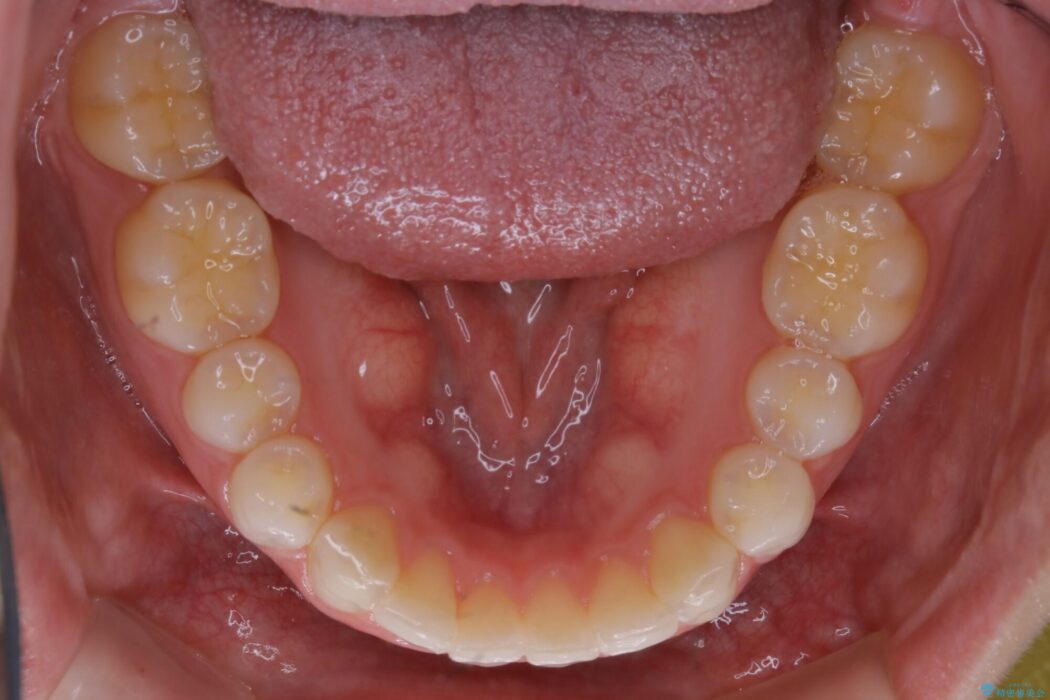

上下前歯のねじれなどで生じている歯列のガタつきをなおしたいとのことで来院されました。

精密検査をしたところ、奥歯に大きな問題がないため移動はほとんど必要がなく、また主訴であるガタつきの改善に必要なスペースも少量であったため、インビザラインのライトパッケージの治療をご提案しました。